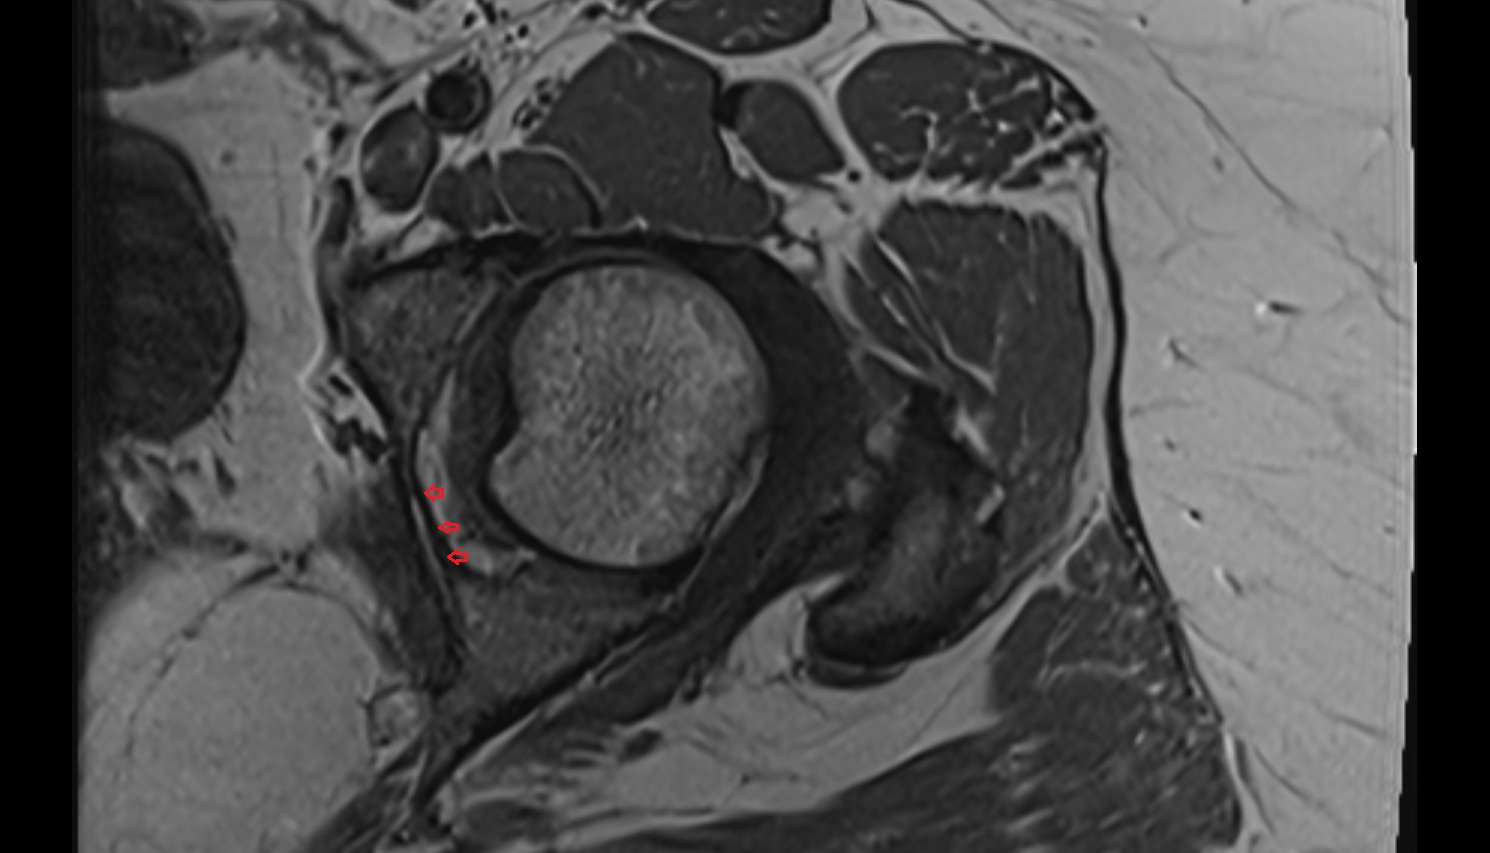

- Acetabular labrum

- Articular capsule of hip joint

- Hip joint